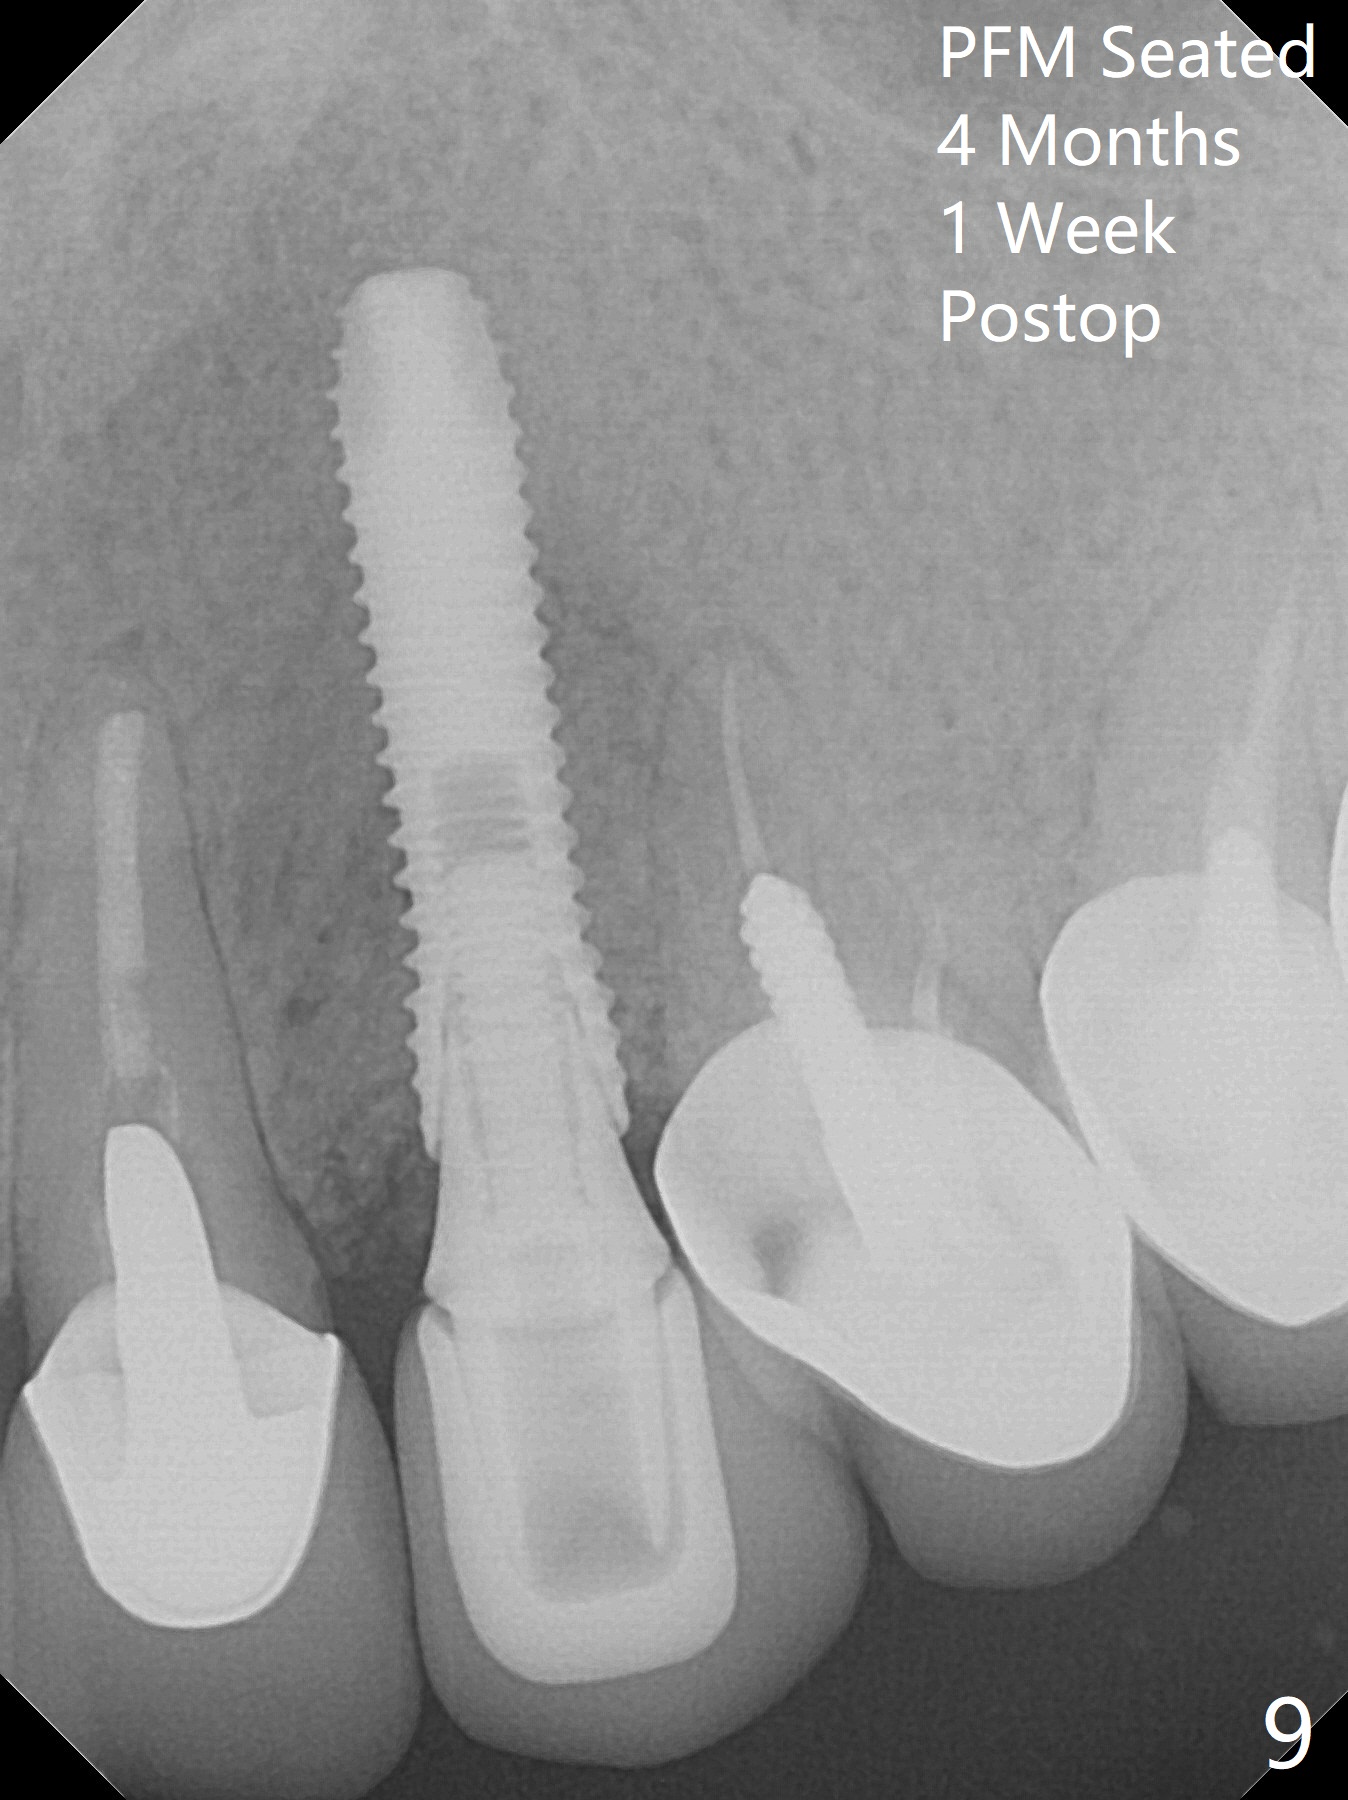

In spite of severe apical infection (Fig1,2 *), a thin narrow strip of the buccal plate (arrowheads, corresponding to the keratinized gingiva) is present when the tooth #11 is extracted. The thin bone keeps the bulging alveolus, i.e., reservoir for bone graft (Vanilla/Osteogen Fig.4 *) after placement of a 3.8x16 mm implant (Fig.3,4). A 4.5x1 mm temporary abutment, placed and trimmed for an immediate provisional, seems to be short in cuff. When an implant is placed deep to prevent periimplantitis, the cuff should be longer, i.e., 3 mm. X-ray should be taken for the depth confirmation after temporary abutment placement. Eight days postop, the mesial gingiva erythema has subsided (Fig.5 < (P: provisional)), while the apical swelling is no longer tender and most likely due to packed bone graft (*). Panoramic X-ray taken 2 weeks postop shows the clearance from the nasal cavity or the maxillary sinus (Fig.6). While the hard tissue around the implant seems to be healthy 5 months postop (Fig.7), the soft tissue is not (Fig.8). The temporary abutment is changed to a cemented one (4.5x5(2) mm) for impression (Fig.8). Since the neighboring crowns are PFM (Fig.6), the new crown will be made of the same material for shade match. Indeed PFM helps shade match in this case as well (Fig.9,10). Switching abutments (from temporary to cemented) makes it difficult to seat the crown. Post cementation X-ray leaves record for future contact loosening. The buccal gingiva remains erythematous associated with open margin (Fig.11 >) 1 year 4 months post cementation. There is no obvious bone loss 1 year 4 months post cementation (Fig.12). It appears that the crown and abutment need to be changed. Although the gingival margin remains erythematous, the gingival hemorrhage is basically lacking due to better oral hygiene during Shelter at Home (1 year 9 months post cementation, Fig.13). Change in abutment and crown will be conducted post coronavirus pandemic. In fact the abutment is incompletely seated (Fig.14 <). In addition, the tooth #12 is symptomatic with PARL associated with the buccal root (*). CBCT indicates possible buccal root fracture (Fig.15,16 ^) and loss of the buccal plate (Fig.16 <).